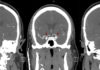

This 82-year-old, right-handed Caucasian gentleman on treatment for hypertension and hyperlipidemia presented with one day of right side facial, arm and leg weakness and slurred speech. On exam, the patient had dysarthria with right upper extremity weakness. The rest of his neurological examination was normal.

Subdural hematomas (SDH) not associated with significant traumatic brain injury (TBI) most commonly occur due to blood accumulation around a superficial parenchymal laceration or tearing of bridging veins or cortical arteries during acceleration-deceleration accidents. They may be more common in patients using anti-platelet or anti-coagulant agents. Once formed, they progress through three phases. First, an initial acute phase (one to three days) occurs during which the clotted blood in the subdural space is thick and electron dense; this appears hyper-dense on non-enhanced CT scans. With time, the blood liquefies and loses its thickness and density entering a sub-acute phase (four days to three weeks). At this point, it appears iso-dense to the brain parenchyma. It eventually enters a chronic phase (>3 weeks) wherein in which the hemorrhage appears hypo-dense to brain parenchyma on non-enhanced CT scans.